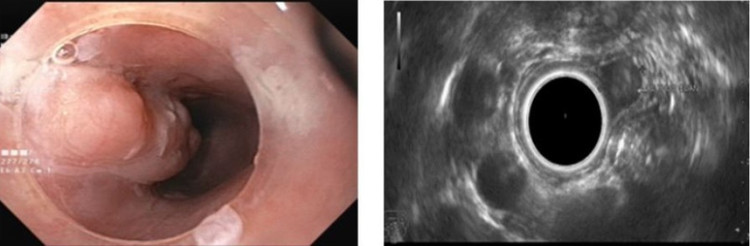

Đó là trường hợp bệnh nhân nữ 37 tuổi trú tại phường Hà An, TX Quảng Yên, Quảng Ninh. Gần đây, bệnh nhân có cảm giác nuốt vướng, nuốt nghẹn nên đến khám tại Bệnh viện Bãi Cháy. Các bác sĩ đã chỉ định nội soi thực quản dạ dày và phát hiện một khối u dưới niêm mạc kích thước lớn với chiều dài lên đến 3cm nằm ở 1/3 trên thực quản. Bệnh nhân ngay sau đó được thực hiện siêu âm nội soi (EUS).

Đây là kỹ thuật tiên tiến, hiện đại trong nội soi có thể xác định được cấu trúc u cũng như vị trí xuất phát u trong thành ống tiêu hóa. Khối u của bệnh nhân được xác định là tổn thương giảm âm nằm ở lớp thứ 2 của thành thực quản.

Hình ảnh khối u trên nội soi ánh sáng trắng và siêu âm nội soi - Ảnh BVCC

Đánh giá khối u kích thước lớn gây nên các triệu chứng khó chịu cho người bệnh, tuy nhiên khối u nằm ở lớp thứ 2 của thành thực quản và còn cơ hội can thiệp cắt bỏ qua nội soi mà không cần phải phẫu thuật.